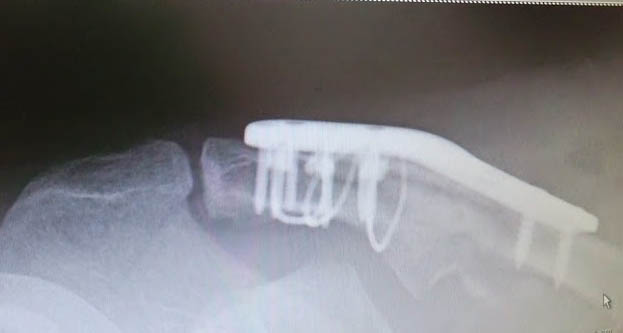

若くてテキパキと事務的でハッキリした先生は

すぐレントゲンを見せてくれた

CTの3Dに見えるのがスゲー!

初めて見ました

骨の仕組みがよくわかります

3分割の骨を

一番長いプレートと6本のネジ

それでも足りないので

ワイヤーで巻き巻きしてみました

先生お疲れ様ー!